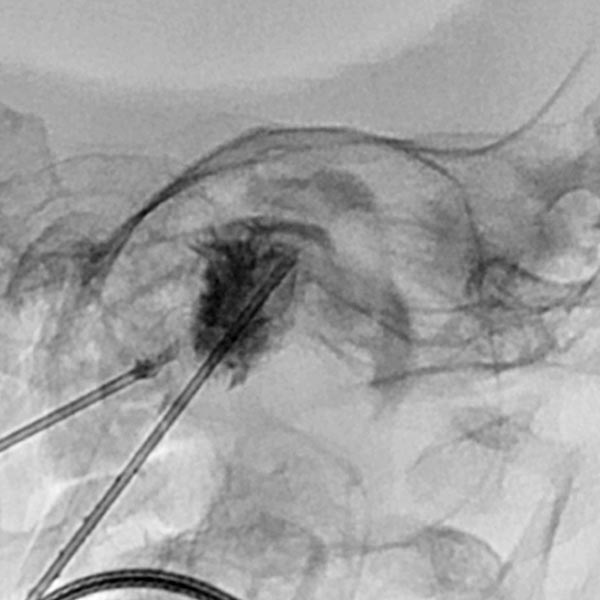

Aufgrund der starken Perfusion der Raumforderung sowie der Ausdehnung in die Orbita wird präoperativ eine Embolisation mit Ethylen-Vinyl-Alkohol-Kopolymer in Direktpunktionstechnik durchgeführt. DSA nach Direktpunktion mit venöser Drainage.

Das Röntgendurchleuchtungsbild zeigt das Embolisat innerhalb der Gefäße schwarz (röntgendicht). Es gelingt superselektiv die Perfusion im Hämangiom stark zu vermindern.